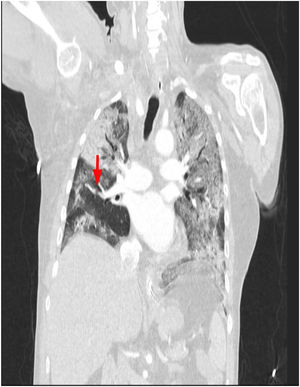

This is the case of a 64-year-old man with a past medical history of hypertension admitted to the ICU with a diagnosis of severe ARDS due to COVID-19-related bilateral pneumonia. The thoracic x-ray reveals a bilateral alveolar-interstitial pattern with damage to the right lung, especially the mid field (Fig. 1, pointer arrows). The blood test results show very high D-dimer levels (28970ng/mL) and due to suspected PTE, a thoracic echocardiography is performed that reveals the presence of RV pressure overload with positive McConnell sign. Following the echocardiographic findings, anticoagulant therapy with low-molecular weight heparin (enoxaparin 1mg/kg/every 12h) is initiated. A thoracic CCTA was performed for diagnostic confirmation purposes that revealed the presence of a repletion defect in the artery of the medial lobe lateral segment (arrows in Figs. 2 and 3) in the PTE setting. Also, the presence of diffuse bilateral damage and extensive areas of cobblestone pattern in a viral infectious process setting (Figs. 2 and 3). The patient remained on anticoagulant therapy until hospital discharge without any associated bleeding complications.